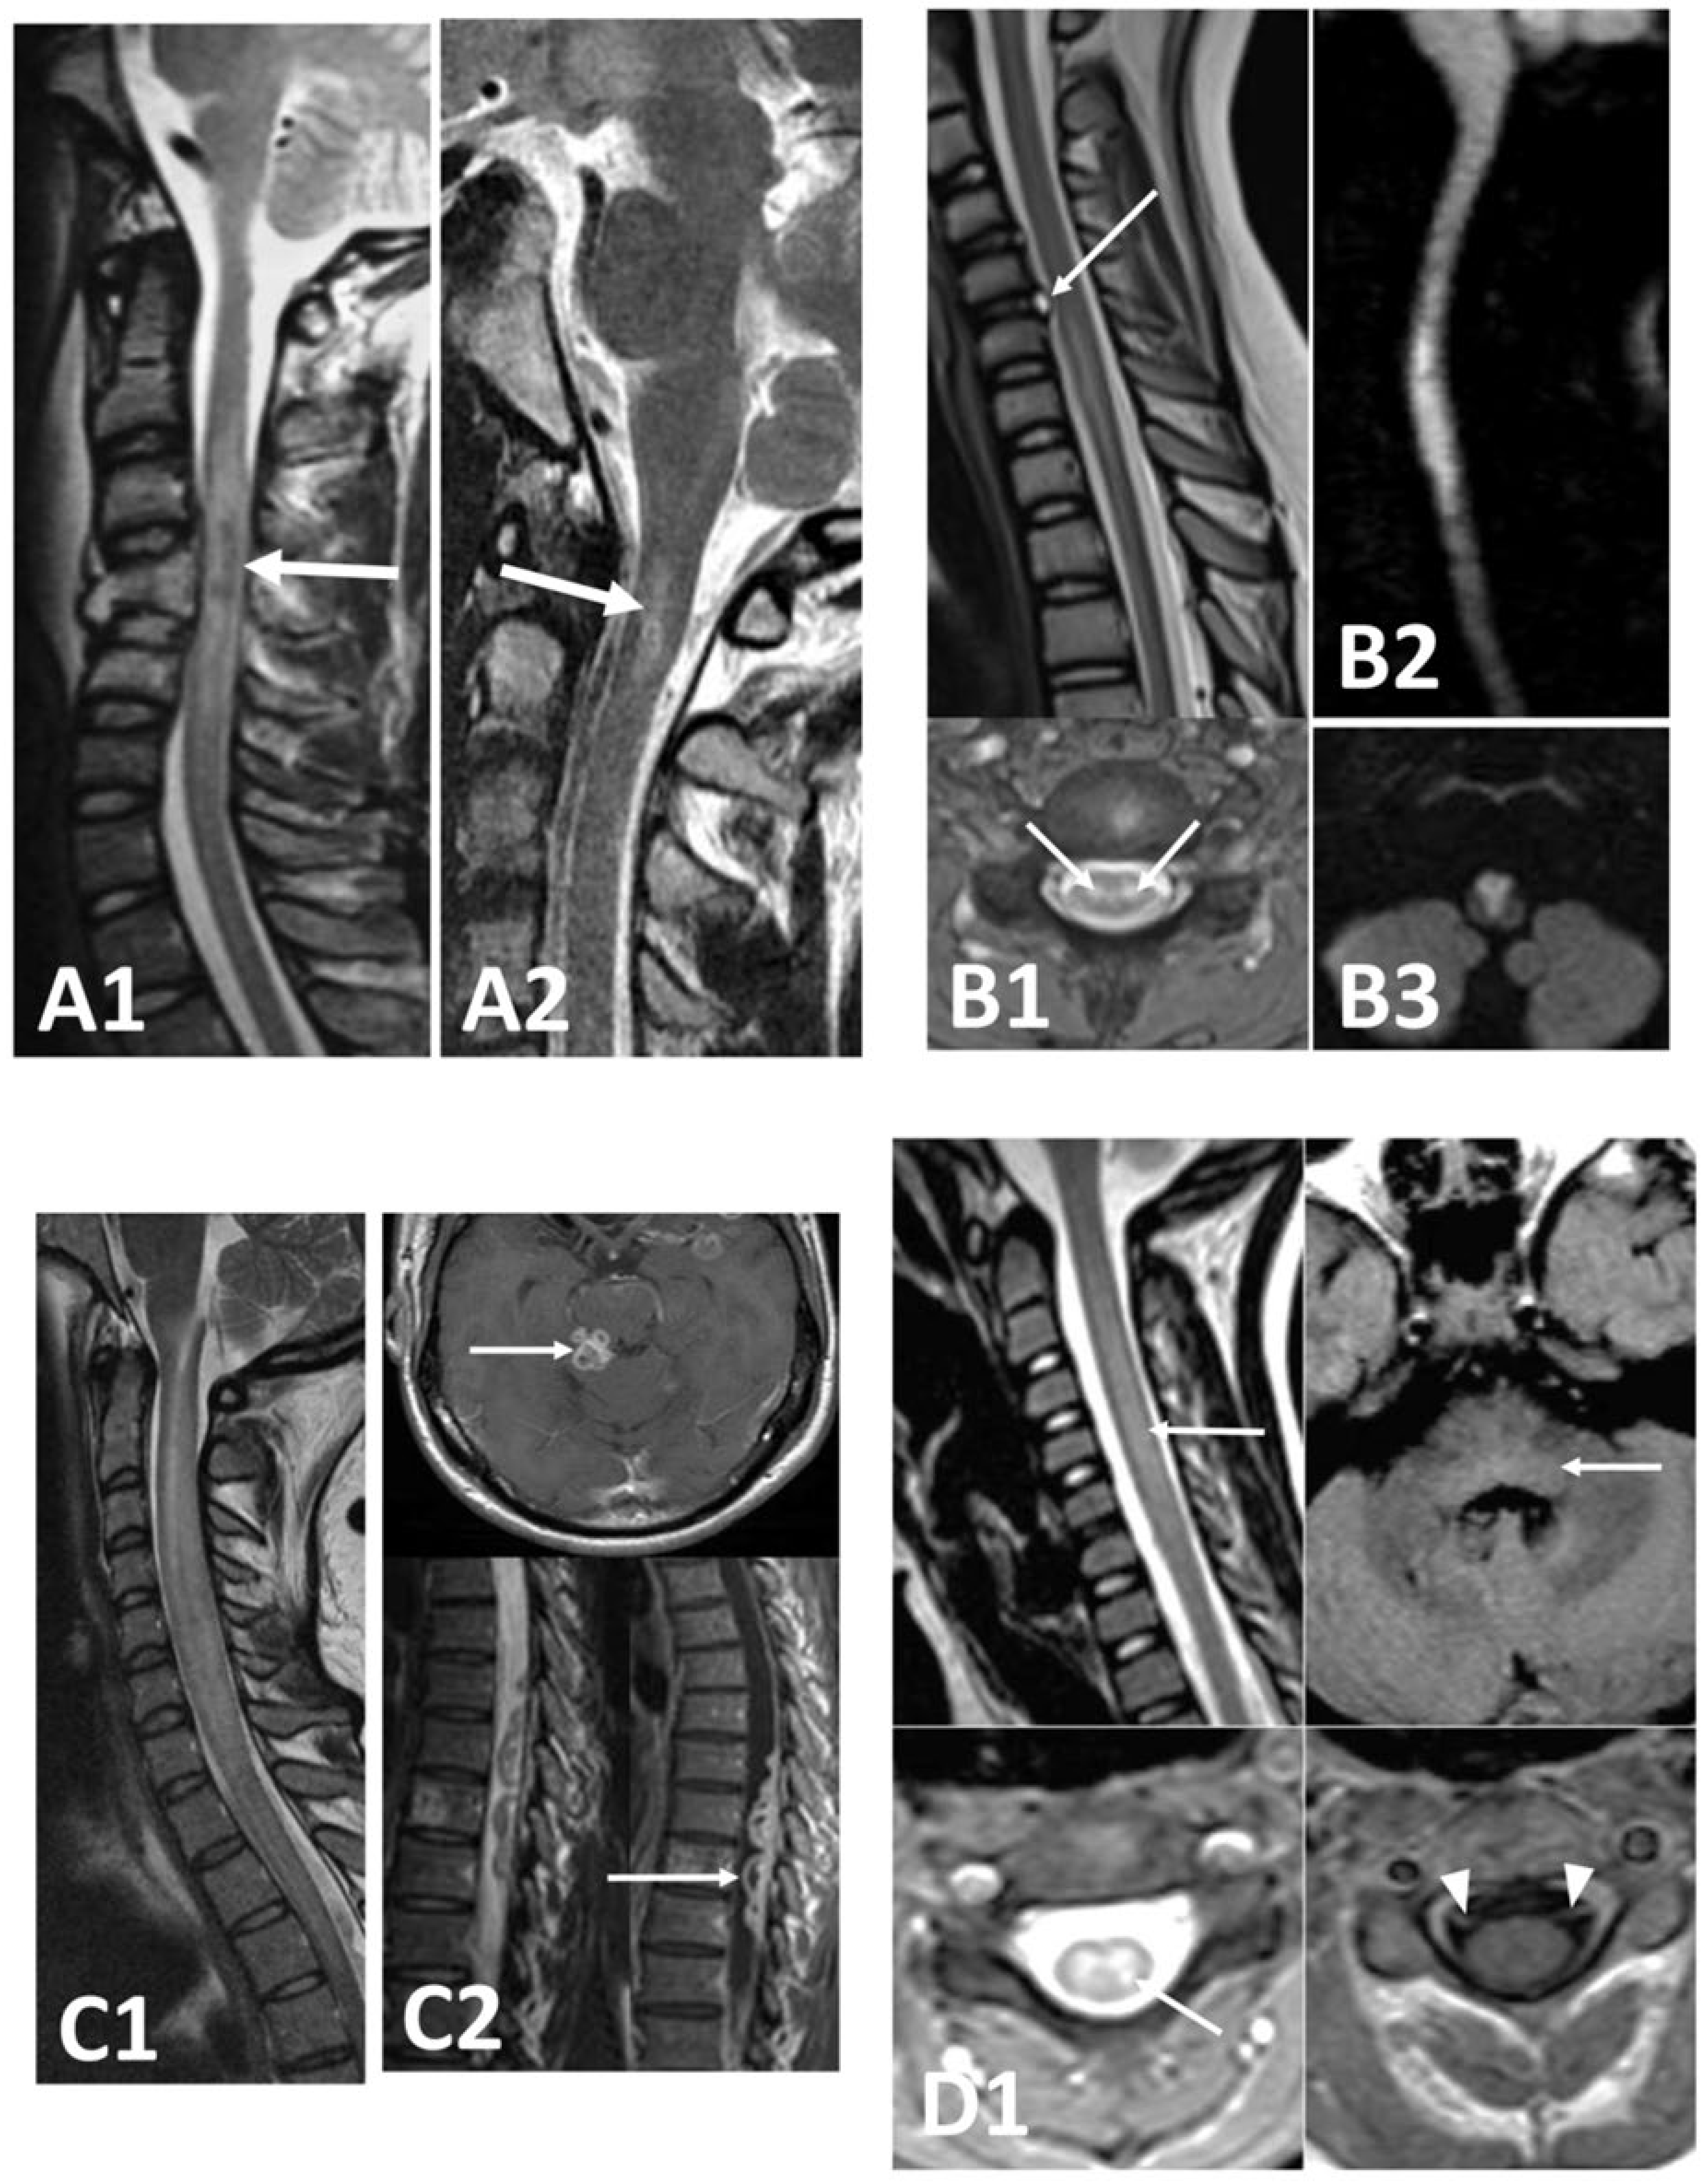

3.3. Inflammatory

3.4. Infectious